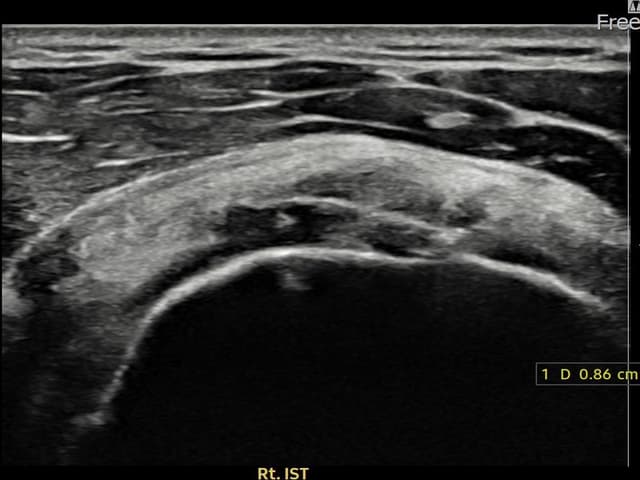

[経過期間: 23.12.14~24.02.22]

[縫縮術] 超音波検査にて右 棘下筋腱 付着部部分断裂(8.6mm × 4mm (腱厚の約45%欠損))を確認。縫縮術施行後、腱の連続性が回復し、日常生活に復帰されました。